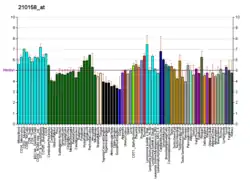

ERCC4 (XPF) in the normal colon

ERCC4 (XPF) is normally expressed at a high level in cell nuclei within the inner surface of the colon (see image, panel C). The inner surface of the colon is lined with simple columnar epithelium with invaginations. The invaginations are called intestinal glands or colon crypts. The colon crypts are shaped like microscopic thick walled test tubes with a central hole down the length of the tube (the crypt lumen). Crypts are about 75 to 110 cells long. DNA repair, involving high expression of ERCC4 (XPF), PMS2 and ERCC1 proteins, appears to be very active in colon crypts in normal, non-neoplastic colon epithelium.

Cells are produced at the crypt base and migrate upward along the crypt axis before being shed into the colonic lumen days later.[32] There are 5 to 6 stem cells at the bases of the crypts.[32] There are about 10 million crypts along the inner surface of the average human colon.[31] If the stem cells at the base of the crypt express ERCC4 (XPF), generally all several thousand cells of the crypt will also express ERCC4 (XPF). This is indicated by the brown color seen by immunostaining of ERCC4 (XPF) in almost all the cells in the crypt in panel C of the image in this section. A similar expression of PMS2 and ERCC1 occurs in the thousands of cells in each normal colonic crypt.

The tissue section in the image shown here was also counterstained with hematoxylin to stain DNA in nuclei a blue-gray color. Nuclei of cells in the lamina propria, cells which are below and surround the epithelial crypts, largely show hematoxylin blue-gray color and have little expression of PMS2, ERCC1 or ERCC4 (XPF). In addition, cells at the very tops of the crypts stained for PMS2 (panel A) or ERCC4 (XPF) (panel C) have low levels of these DNA repair proteins, so that such cells show the blue-gray DNA stain as well.[31]

ERCC4 (XPF) deficiency in the colon epithelium adjacent to and within cancers

ERCC4 (XPF) is deficient in about 55% of colon cancers, and in about 40% of the colon crypts in the epithelium within 10 cm adjacent to the cancers (in the field defects from which the cancers likely arose).[31] When ERCC4 (XPF) is reduced in colonic crypts in a field defect, it is most often associated with reduced expression of DNA repair enzymes ERCC1 and PMS2 as well, as illustrated in the image in this section. Deficiencies in ERCC1 (XPF) in colon epithelium appear to be due to epigenetic repression.[31] A deficiency of ERCC4 (XPF) would lead to reduced repair of DNA damages. As indicated by Harper and Elledge,[33] defects in the ability to properly respond to and repair DNA damage underlie many forms of cancer. The frequent epigenetic reduction in ERCC4 (XPF) in field defects surrounding colon cancers as well as in cancers (along with epigenetic reductions in ERCC1 and PMS2) indicate that such reductions may often play a central role in progression to colon cancer.

Although epigenetic reductions in ERCC4 (XPF) expression are frequent in human colon cancers, mutations in ERCC4 (XPF) are rare in humans.[34] However, a mutation in ERCC4 (XPF) causes patients to be prone to skin cancer.[34] An inherited polymorphism in ERCC4 (XPF) appears to be important in breast cancer as well.[35] These infrequent mutational alterations underscore the likely role of ERCC4 (XPF) deficiency in progression to cancer.